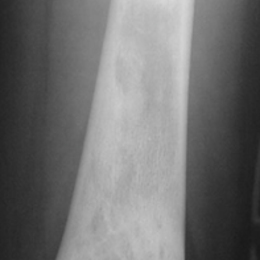

Radiographic imaging is used to help form a diagnosis. These include X-Ray, MRI, CT and Bone Scans

An example of a X-Ray is shown.